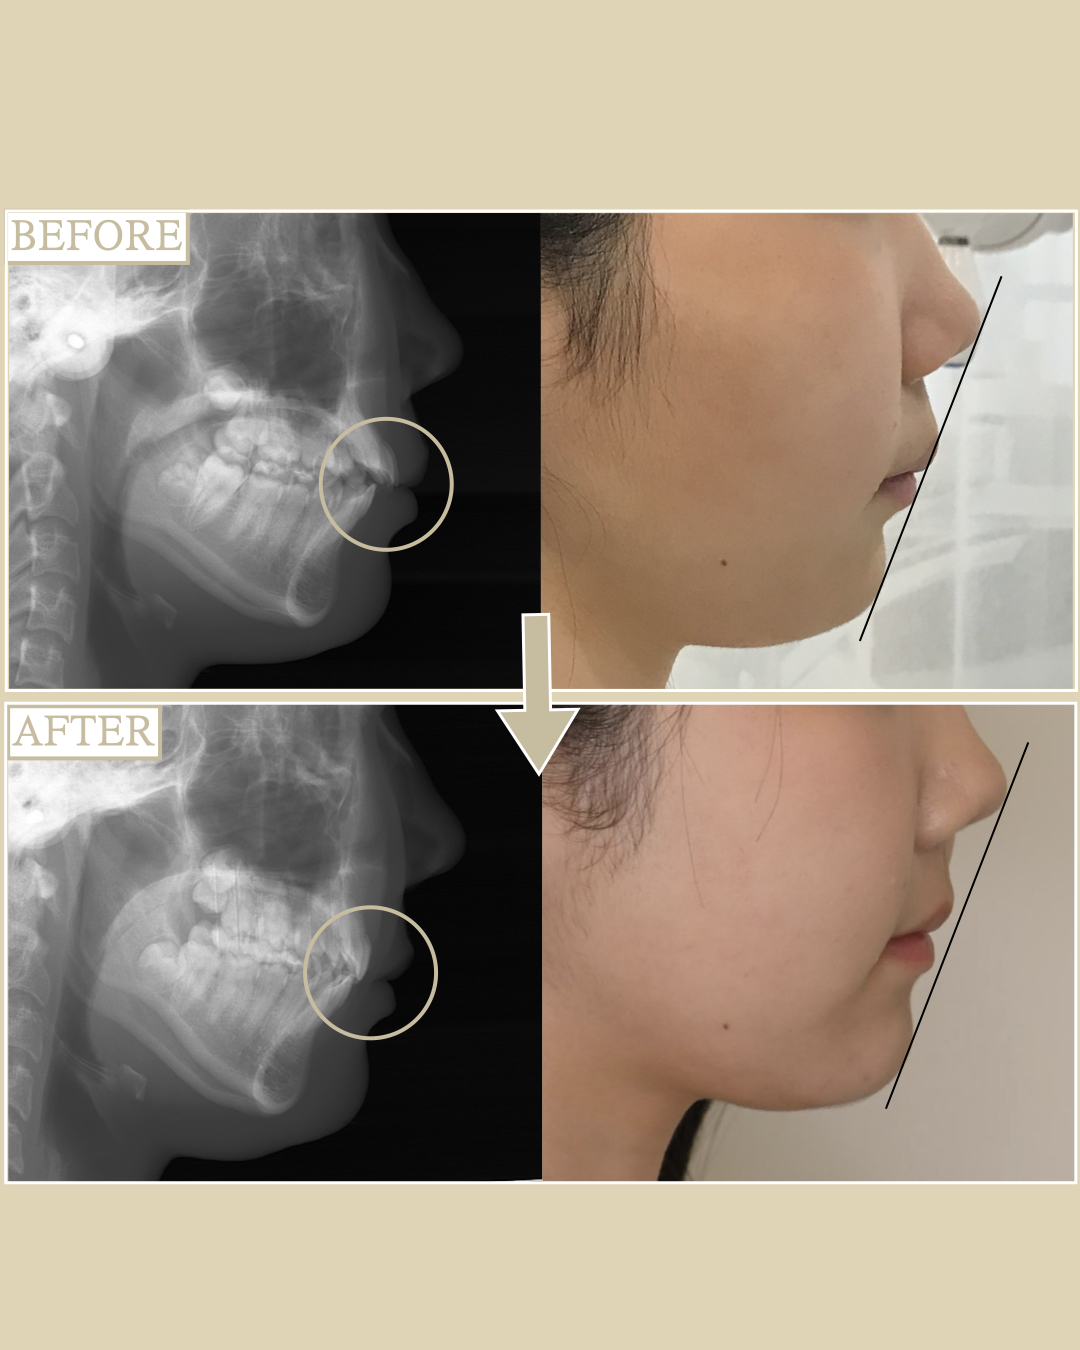

- 主訴:出歯が気になる

- ①出っ歯のため前歯で噛めないので、奥歯のみで力の負担を支えている状態です。

そのため、将来的に奥歯からグラグラしてきたり破折しやすいことが問題として考えられます。

②顔貌を横から見たときに、出っ歯であるためCカールリップという鼻下から上唇の間にある人中に丸みがなく、人中が長く見えてしまう事と顎に立体感がないため少しのべっとした印象になります。

- 出っ歯のため、上の左右4番目を抜歯をして歯が移動できるスペースを作り、表側ワイヤー矯正にて出歯の改善と正しい噛み合わせ(全体的にに噛み合っている状態)に改善

①出っ歯が改善され、噛み合わせも犬歯関係1級で臼歯関係で2級仕上げで全体的にバランスのとれた健康的な歯並びへと改善されました。

②横顔も矯正前からEラインに唇が収まっている患者様でしたが、矯正により出歯を後ろに引いたことで、Cカールリップができ、顎先に少しボリュームが出たことにより永久的に立体感のある横顔になりました。また相乗効果で口元が引っ込んだ事で鼻が高くみえます。